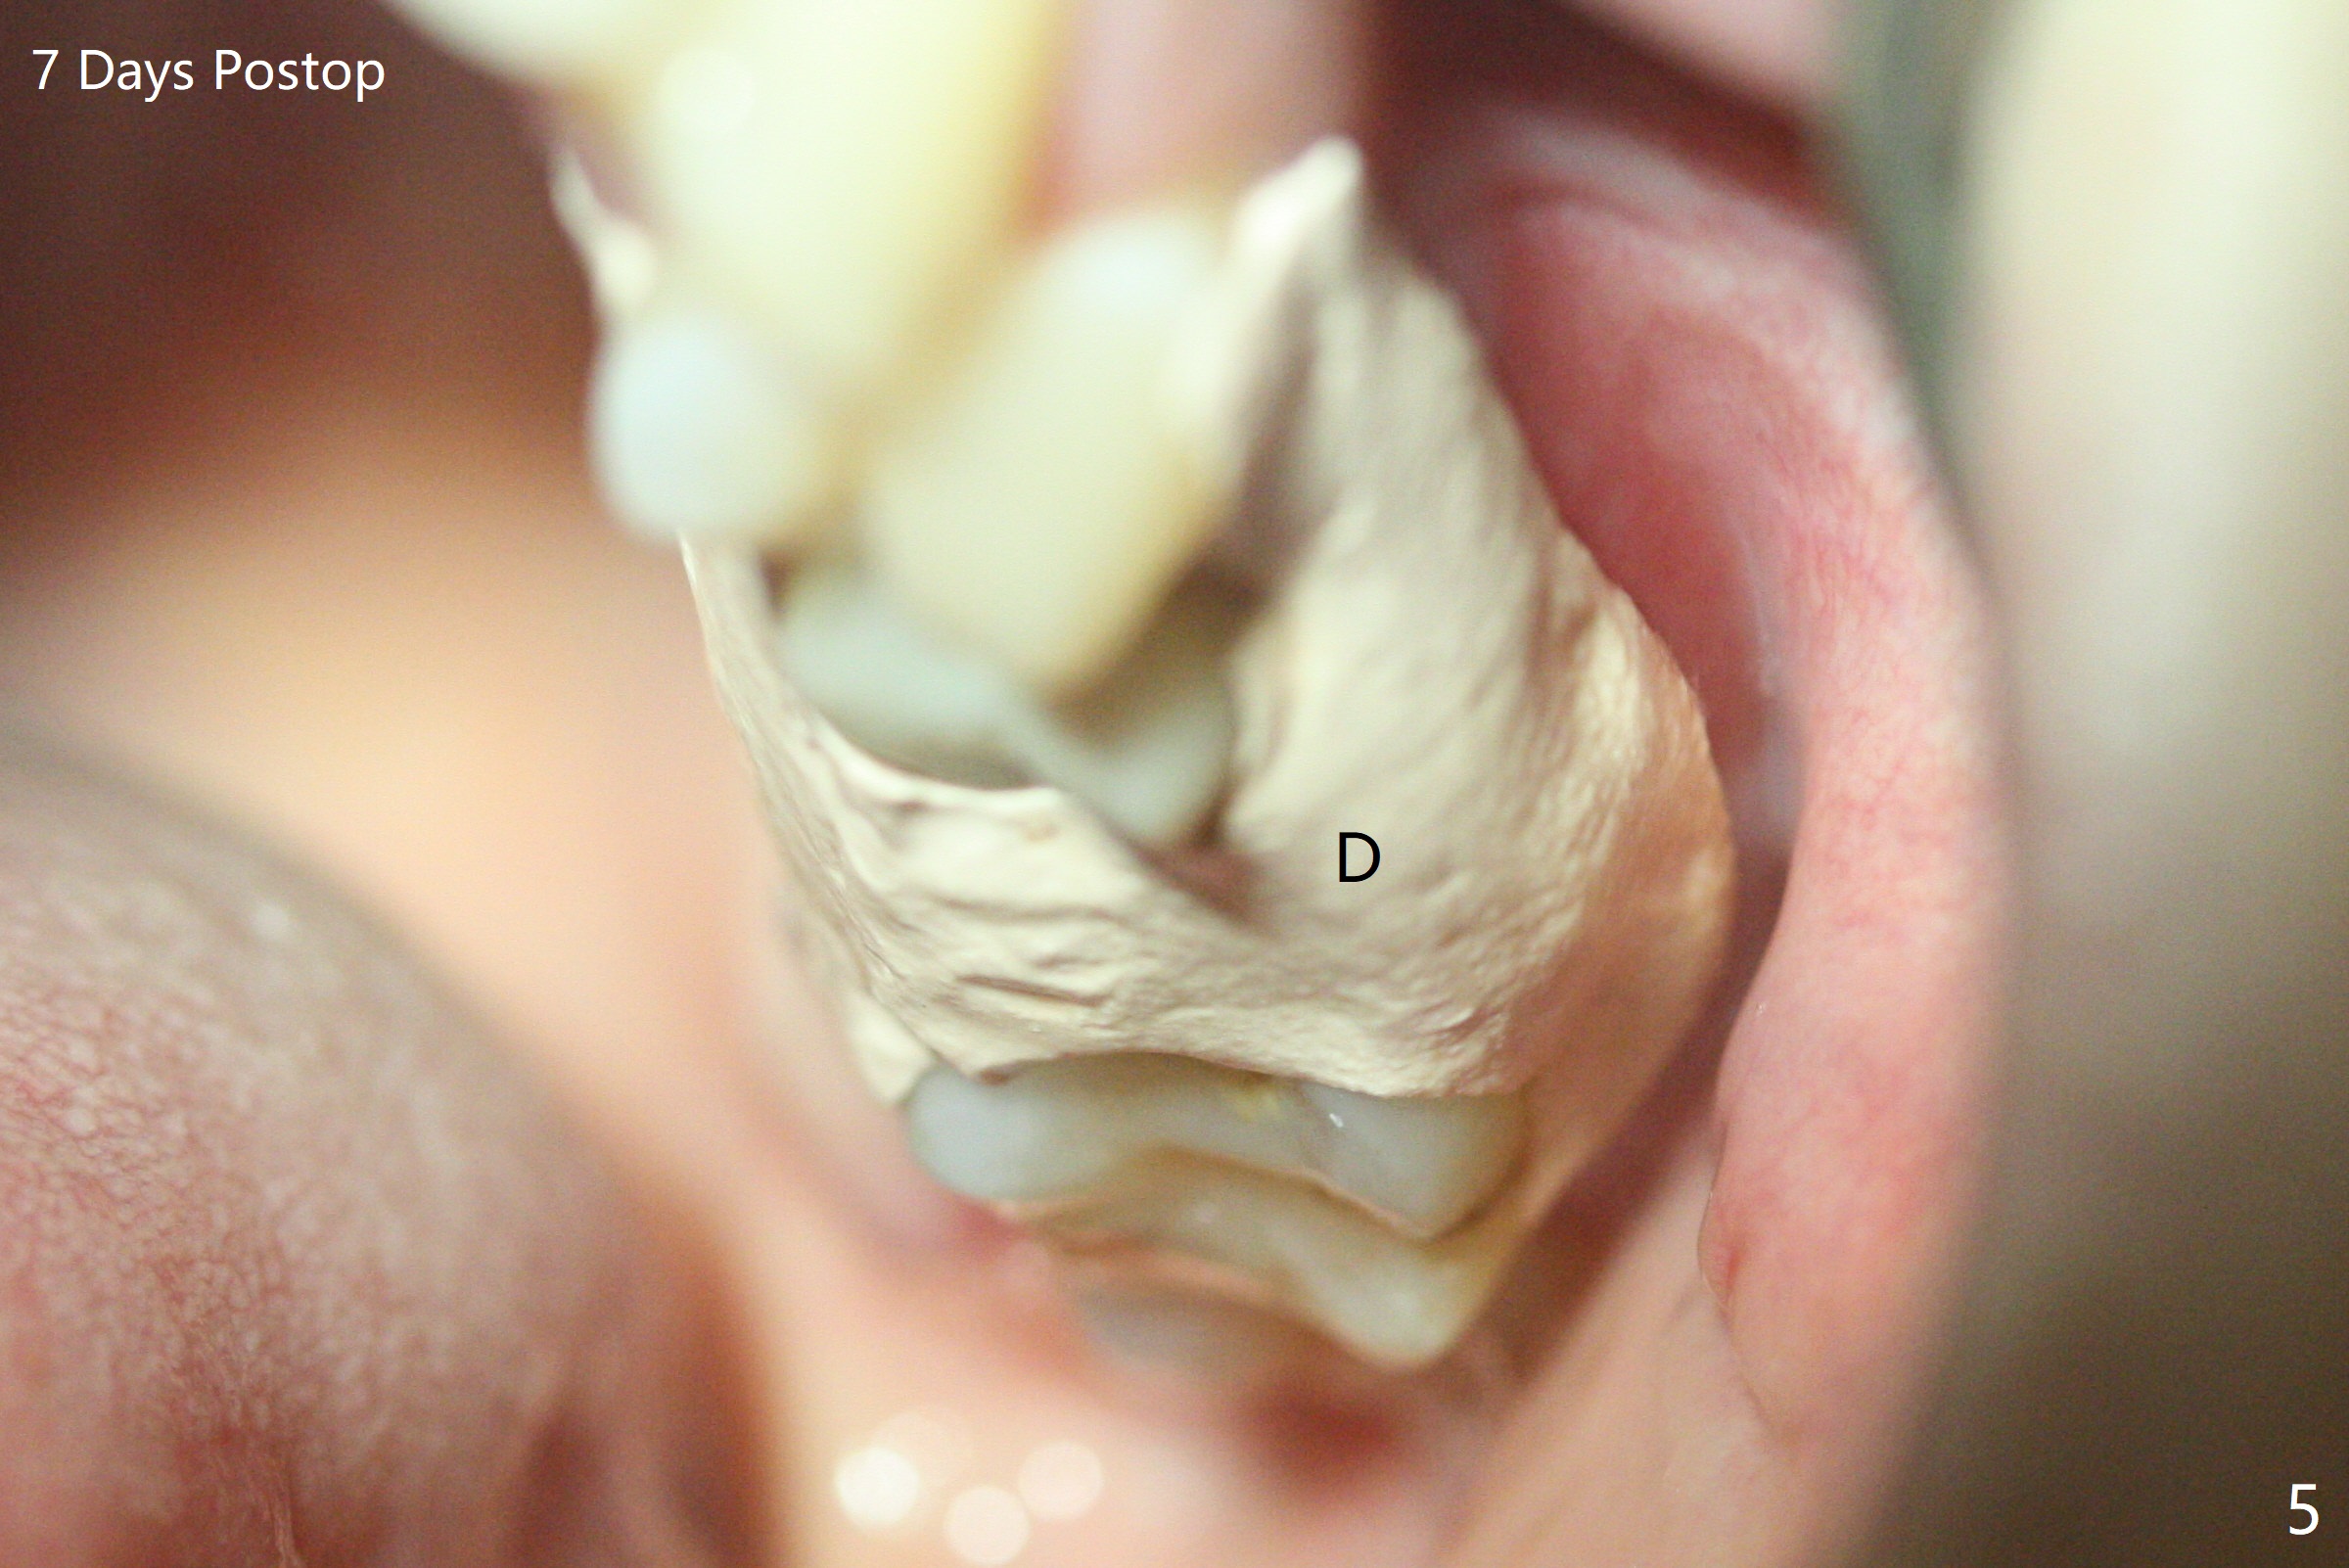

A 32-year-old woman develops periimplantitis (severe hemorrhage and deep pockets) at #14 three years 7 months post cementation (Fig.1).  A 4.5x11 mm implant is placed with flap at #13 after failure for the 1st time (Fig.2), while a 5x11 mm implant is placed flapless with sinus membrane perforation.  Uniposts are cemented with Ketac.  The lingual plate at #14 is defective (Fig.3).  The implant at #14 will be removed flapless, followed by Osteogen plug (most likely sinus floor defect) and bone graft.  After healing, an implant will be placed with guide.  By breaking the proximal contacts, the crown, abutment and implant at #14 are shaken loose using forceps.  Finally the crown breaks off.  Make a slot on the top of the abutment and use a screw bit to turn the abutment/implant counterclockwise.  There is abundant granulation tissue with arterial hemorrhage associated with granulation tissue removal.  The defect involves the distal surface of the implant at #13 and the mesial surface of the tooth #15.  Therefore bone graft is deposited in these surfaces (Fig.4 arrowheads, as compared to preop BW, Fig.4').  The periodontal dressing seems to remain in place asymptomatic 7 days postop (Fig.5).  The bone height 5.5 months postop should be enough for implantation (Fig.6).  To avoid marker associated with guided surgery, free hand will be adopted.  Sinus lift with PRF is expected.  To place in the middle of the ridge buccopalatally, incision will be made with bone expansion.